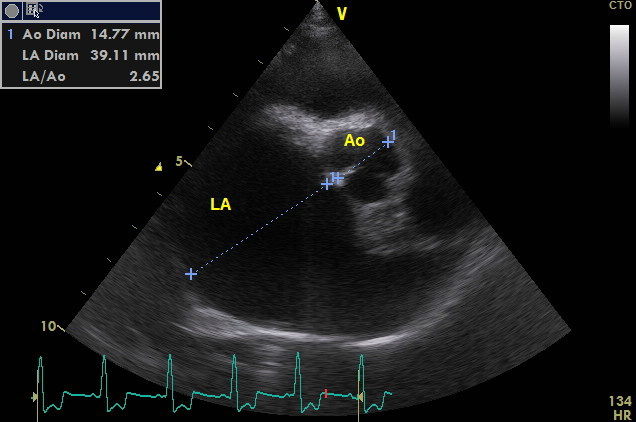

Durch die Herzultraschalluntersuchung konnte dann leider der Verdacht auf eine deutlich weiter fortgeschrittene Herzerkrankung bestätigt werden. Neben einer hochgradigen Vergrößerung der linken Herzhälfte durch die Klappeninsuffizienz ließ sich außerdem ein moderat erhöhter Druck in den Lungenarterien feststellen. Dies nennt man Pulmonale Hypertension oder Lungenhochdruck. Für eine solche Erhöhung des Blutdruckes im Lungenkreislauf gibt es unterschiedliche Ursachen. Eine davon ist ein bestehendes Lungenödem durch ein Linksherzversagen, wie es bei Alf nun offensichtlich der Fall war. Da die Diagnose nun „dekompensierte Mitralklappenendokardiose“ - oder nach der CHIEF - Klassifizierung Stadium C2 * - lautete, verordnete ich dem kleinen Hund zusätzlich zwei weitere Medikamente zur dauerhaften Herztherapie (eines zur Entwässerung und das andere zur Entlastung des Herzens durch Weitstellung der Arterien und zur Unterstützung der Pumpfunktion des Herzmuskels). Die am Morgen im Wald aufgetretene „Synkope“ ließ sich also eindeutig durch die fortgeschritten Herzerkrankung erklären.